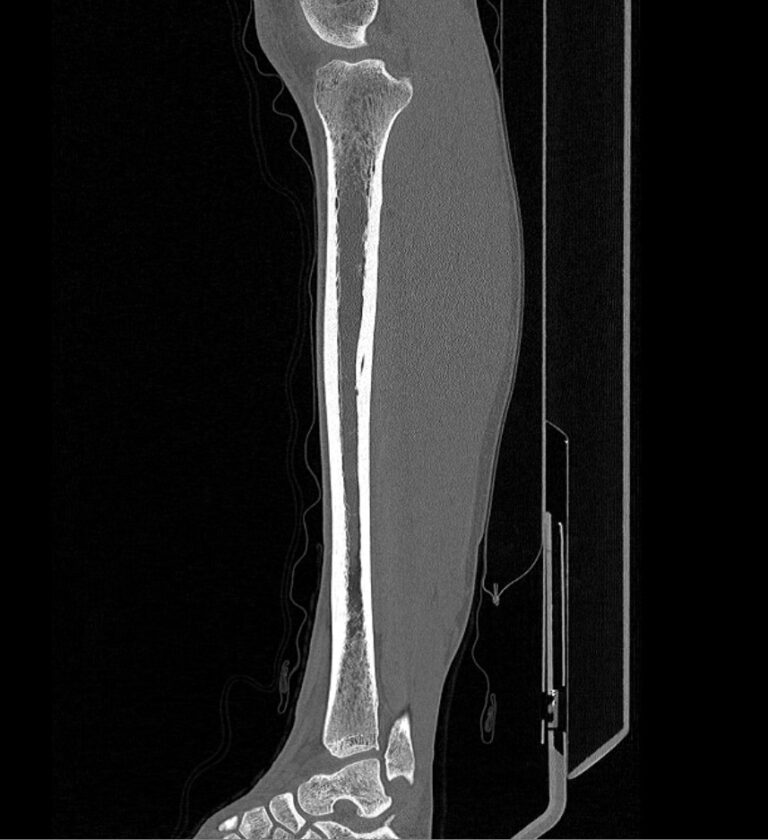

Наиболее информативным методом исследования костных структур и мягких тканей голени является мультиспиральная компьютерная томография. КТ относится к лучевым методам исследования и основана на применении ионизирующего излучения и последующей цифровой обработке данных, полученных при КТ-сканировании.

В наших медицинских центрах обследование области голени проводится на современных мультиспиральных компьютерных томографах последнего поколения TOSHIBA AQUILION. При помощи рентгеновских лучей аппараты послойно сканируют исследуемую область с толщиной среза от 0,5 мм. В результате получаются детальные снимки и цифровые трехмерные изображения в мельчайших подробностях. При этом пациент получает уменьшенную дозу рентгеновского облучения.

Мультиспиральная компьютерная томография позволяет оценить структуру костей голени, выявить переломы, воспалительные изменения, участки деструкции костной ткани, диагностировать опухолевые образования.